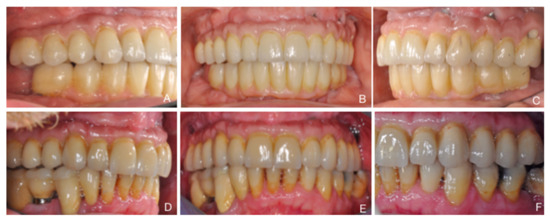

| Male | Female | Mean Age | Smokers | Maxilla | Bone Type 1 I, II, III, IV | Insertion Torque 1 (Ncm) | Antagonist 1 | |

|---|---|---|---|---|---|---|---|---|

| 3 | 3 | 59.8 | 4 out of 6 | 16 and 26 | Type I: 0 Type II: 0 Type III: 6 Type IV: 6 | <15: 0 15 < x< 35: 6 ≥35: 6 | ND: 2 FDP: 2 OD: 0 Mix: 8 | |

| STANDARD | 3 | 2 | 60.8 | 2 out of 5 | 16 and 26 | Type I: 0 Type II: 0 Type III: 6 Type IV: 4 | <15: 0 15 < x < 35: 6 ≥35: 4 | ND: 2 FDP: 0 OD: 2 Mix: 6 |